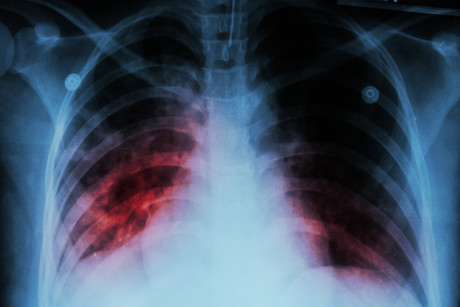

Researchers at Sydney’s Centenary Institute have come one step closer to developing a more effective vaccine against the world’s deadliest infectious disease, demonstrating how an Influenza A-based vaccine can be used to activate immune cells in the lungs — and help protect against tuberculosis in the process.

As the world’s single most deadly infectious disease, tuberculosis is a serious threat both worldwide and in our immediate region, with more than 50% of cases occurring in the Asia–Pacific region. Currently, a vaccine known as BCG is given to babies and young children to immunise them against tuberculosis; however, its immunity wanes after about 15 years, meaning it is largely ineffective in adults.

Seeking to solve this problem, Centenary researchers have demonstrated how a subunit vaccine (based on the Influenza A virus) can be used to activate special memory T-cells in the lungs, which in turn helps protect against tuberculosis. Five years in the making and now published in the journal Mucosal Immunology, their study has led to a significant breakthrough in the quest to eliminate tuberculosis.